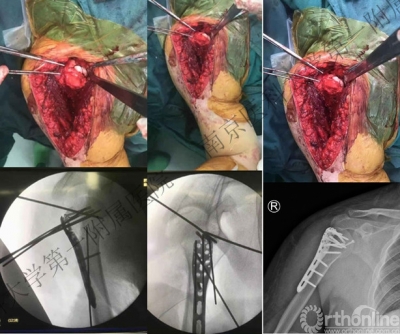

胸大肌——三角肌间隙入路

九、外科技术要点

(一)充分显露肱骨头是治疗成功的先决条件:

- 是解除肱骨头与肩胛盂交锁的前提。

- 是修复反Hill-Sach损伤的前提。

- 以肱二头肌长头为标志切开肩袖,帮助显露肱骨头。

(二)切开肩胛下肌(是进一步显露肱骨头关节面的钥匙)

可能损伤腋神经,降低肩胛下肌肌力;但尽可能保护了骨性结构的完整,利于复位解剖颈骨折。

切开部分肩胛下肌后于肩胛盂前方插入骨撬,帮助显露反Hill-Sachs损伤。

(三)肱骨小结节截骨

显露更为充分,小结节骨块可用于修复反Hill-Sachs损伤;但增加了骨折复位的难度。伴有小结节骨折时更便于处理。

(四)复位脱位的肱骨头

1.用两枚3.5mm克氏针钻入肱骨头内,固定主要的肱骨头骨折块并把持肱骨头,利用Joy-Stick技术将肱骨头牵开、外旋、复位。

2.避免在肱骨头和关节盂之间插入骨撬的方法来复位肱骨头,会加重肱骨头关节面的损伤。

(五)修复反Hill-Sachs损伤

1.外旋肱骨头,显露肱骨头关节面损伤处。

2.改良McLaughlin术、 Underpinning术、球囊扩张术。

3.Dubousset 方法:对肱骨头关节面压缩性骨折均给予直视下复位、填充植骨、螺钉固定,手术指征不受压缩部分占总关节面面积比例的限制。

(六)评估肩关节的稳定性

1.修复反Hill-Sachs损伤、固定肱骨近端骨折后,内旋肱骨头,检查肩关节的后向稳定性。

2.绝大多数情况下肩关节后方均稳定,无需进一步修复后方的韧带结构。